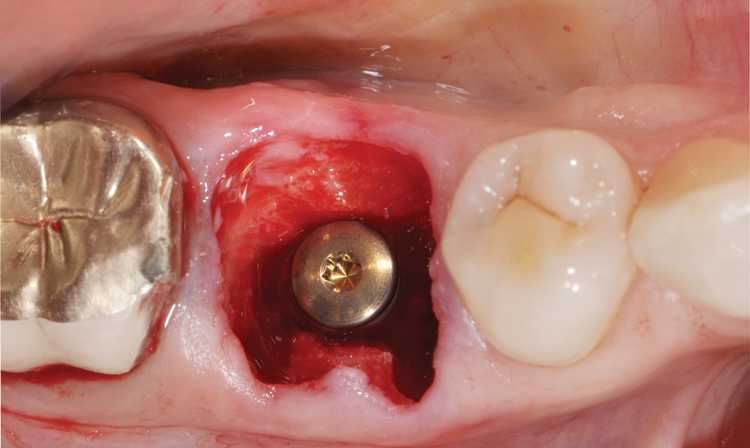

In the molar region, the preparation of sites with large septa presents its own challenges, especially when carried out in an analog fashion. Fully guided preparation of the osteotomy and implant placement reduces the potential for the drill to drift or the implant to migrate into the adjacent socket defects (Figure 5 through Figure 9).

(7.) Restoratively centered guided osteotomy and implant insertion.

Figure 7

(8.) Restoratively centered guided osteotomy and implant insertion.

Figure 8